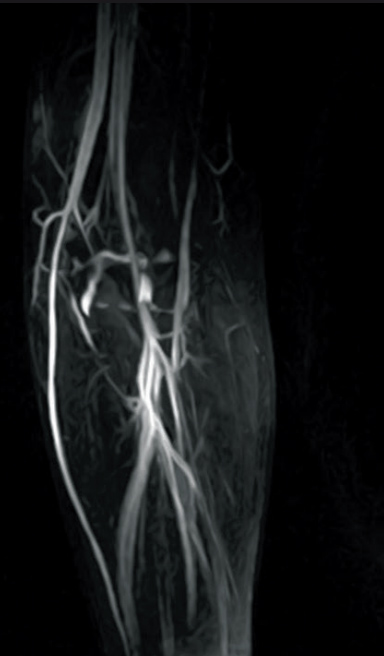

2D-TOF MIP image